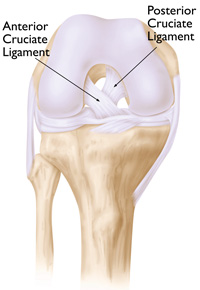

In a healthy knee, ligaments support the joint.

As the name implies, the posterior cruciate ligament is kept with this implant design (the anterior cruciate ligament is removed). Cruciate-retaining implants do not have the center post and cam design. This implant may be appropriate for a patient whose posterior cruciate ligament is healthy enough to continue stabilizing the knee joint.

In most total knee replacement procedures, the anterior cruciate ligament is removed to allow for precise placement of the implant. In bicruciate-retaining designs, both the anterior and posterior cruciate ligaments are kept. The rationale for this type of design is that by saving both ligaments, the knee will function and feel more like a non-replaced knee.